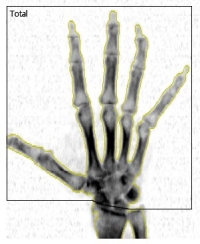

Kości obu rąk |

|

Wysoce specjalistyczna procedura, przeznaczona dla pacjentów w diagnostyce bólów i obrzęków drobnych stawów rąk w przebiegu różnych procesów zapalnych. Umożliwia monitorowanie zmian gęstości mineralnej kości rąk (ang. bone mineral density - BMD).